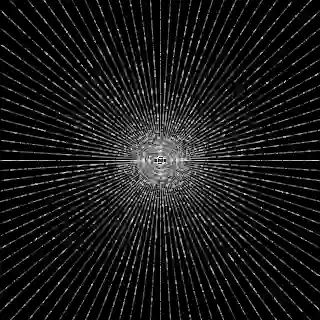

This article presents a novel undersampled magnetic resonance imaging (MRI) technique that leverages the concept of Neural Radiance Field (NeRF). With radial undersampling, the corresponding imaging problem can be reformulated into an image modeling task from sparse-view rendered data; therefore, a high dimensional MR image is obtainable from undersampled $k$-space data by taking advantage of implicit neural representation. A multi-layer perceptron, which is designed to output an image intensity from a spatial coordinate, learns the MR physics-driven rendering relation between given measurement data and desired image. Effective undersampling strategies for high-quality neural representation are investigated. The proposed method serves two benefits: (i) The learning is based fully on single undersampled $k$-space data, not a bunch of measured data and target image sets. It can be used potentially for diagnostic MR imaging, such as fetal MRI, where data acquisition is relatively rare or limited against diversity of clinical images while undersampled reconstruction is highly demanded. (ii) A reconstructed MR image is a scan-specific representation highly adaptive to the given $k$-space measurement. Numerous experiments validate the feasibility and capability of the proposed approach.